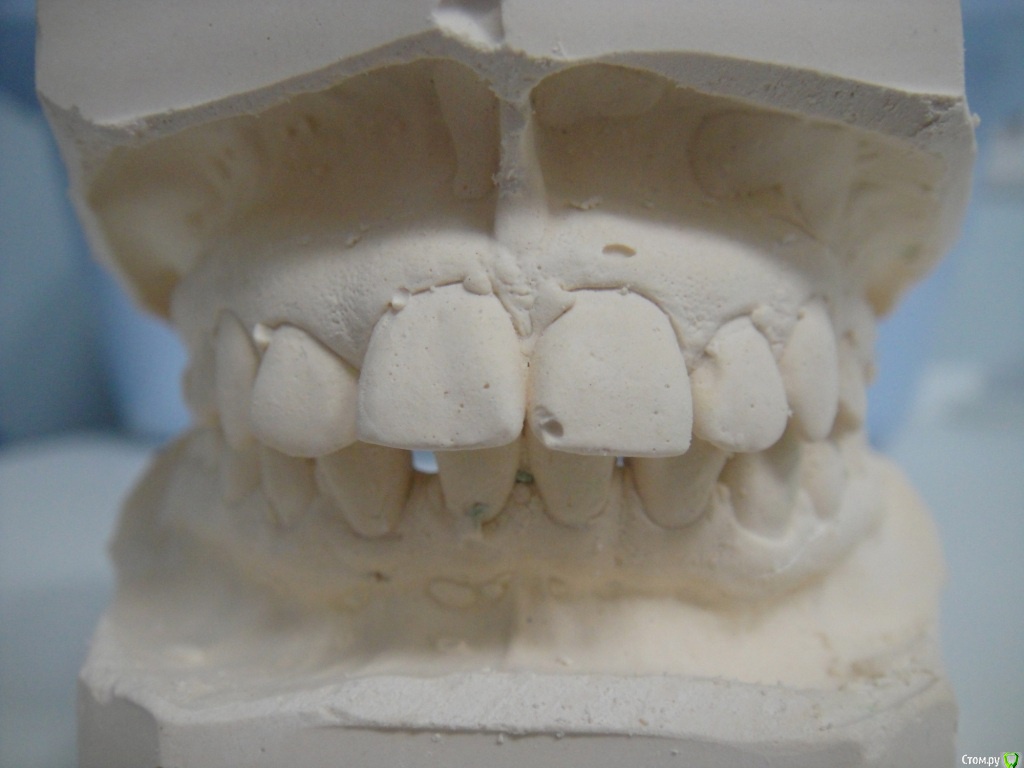

Брекеты ношу 2 месяца, мне 26 лет. Прикрепила фото открытой улыбки уже в брекетах, но так практический никогда не улыбаюсь, неудобно, (торчат два передних зуба) - "рот не открывается"  :D. Еще есть фото зубов с разных сторон, если слепков не хватит, могу добавить.

По Трг Вам однозначно необходимо удаление зубов на в.ч, а возможно и на н.ч т.к очень сильный наклон передних зубов.